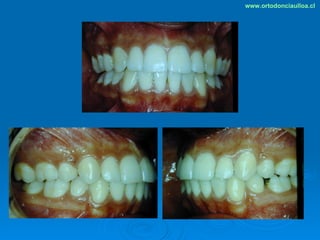

Este documento presenta dos casos clínicos de pacientes que recibieron tratamiento de ortodoncia. El primer caso fue de una paciente femenina de 14 años con apiñamiento dental y mordida cruzada que fue tratada mediante extracción de premolares y alineamiento dental. El segundo caso fue de un paciente masculino de 14 años con clase II esqueletal y desarmonía dentomaxilar que fue tratado con extracción de premolares y corrección de mordida. Ambos casos mostraron mejoría después de 3 años de tratamiento.